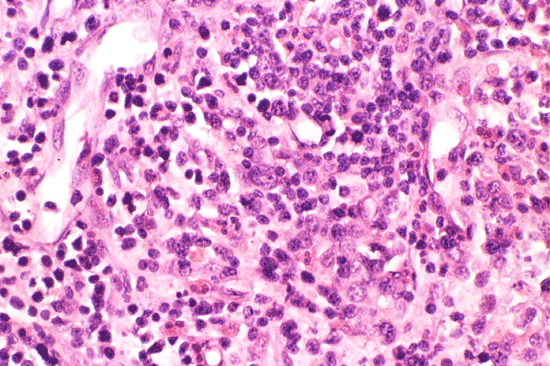

A bone marrow biopsy was performed. The followings are representative photos taken from the bone marrow biopsy:

Com401-1-B1.gif (137270 bytes) Com401-1-B2.gif (127871 bytes) Com401-1-B3.gif (174580 bytes) Com401-1-B4.gif (156845 bytes) Com401-1-B5.gif (138860 bytes)